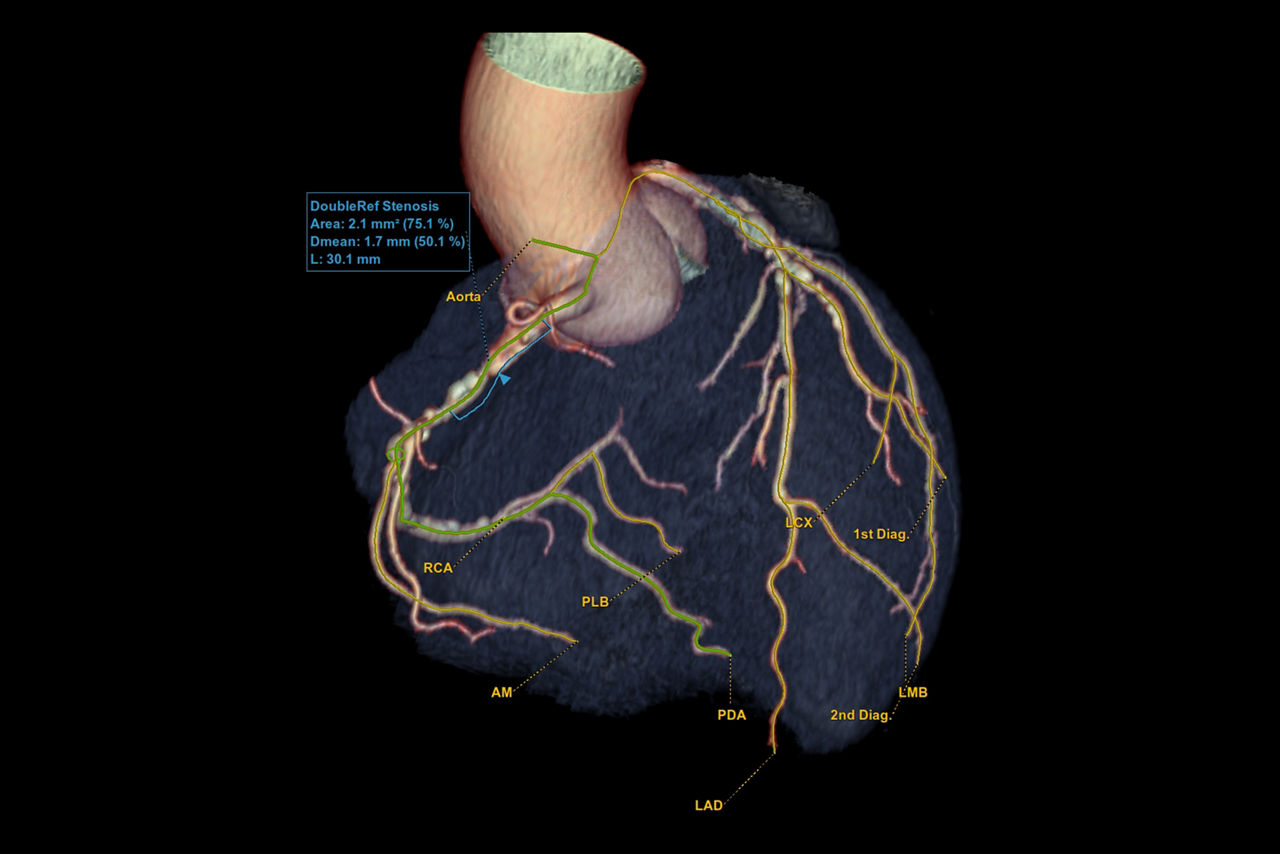

• Auto Coronary analysis automatically segments the coronary tree, tracks and labels the coronary arteries

• Relative perfusion color codes and quantifies percent of hypo-dense areas of myocardium with four selectable color maps and fusion overlays with the coronary tree

• Plaque ID provides volume measurements for four distinct Hounsfield ranges to aid with identification and visualization of coronary plaque